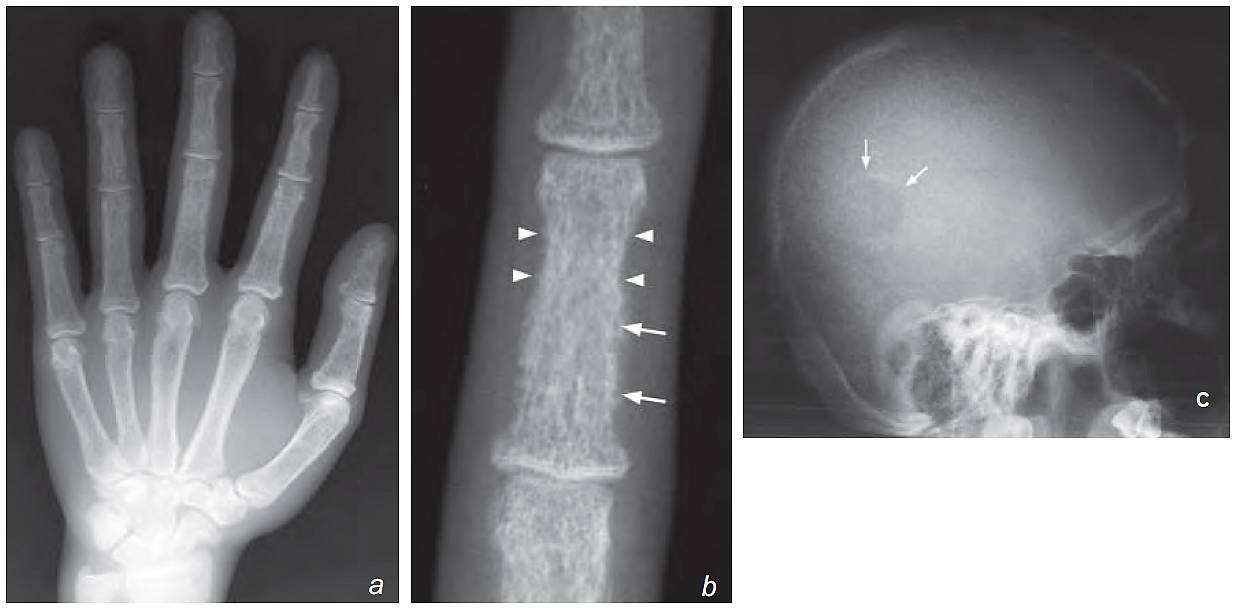

- Lateral skull view:

- Mottled calvarium (salt and pepper skull)

- Blurred inner and outer tables

- Well-defined lucent lesion in the parietal bone

c) Lateral view of the skull shows blurring of inner and outer tables of the skull (normally of distinct borders). There is also a generalized mottled appearance which is due to widespread granular bone resorption. This is termed a salt and pepper skull. There is a well-defined lucent lesion in the parietal bone indicating a Brown tumour (arrows)

- Brown tumour (osteoclastoma) – well-defined cystic lesion in affected bone, representing a focal mass of osteoclasts and fibrous tissue . Commonly in skull, femur and pelvis.